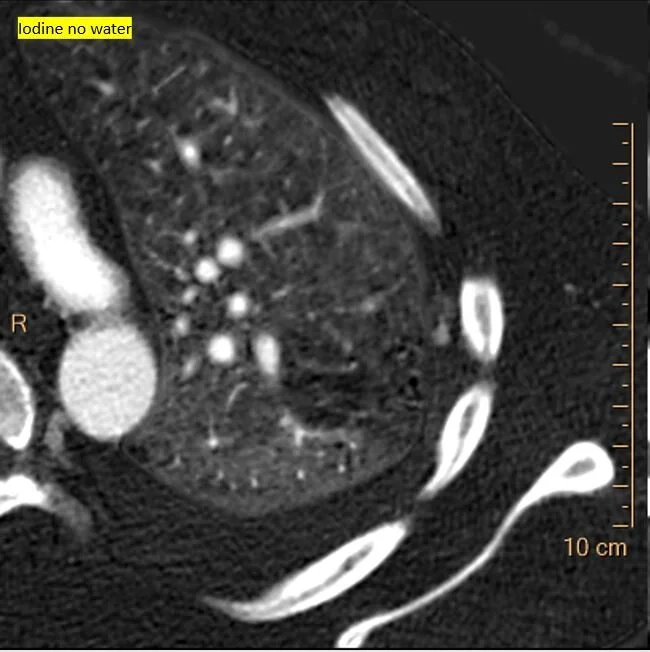

Iodine map shows focal nodule of uptake in the pleural thickening

Iodine overlay confirms the finding. This is what bled a few days later.